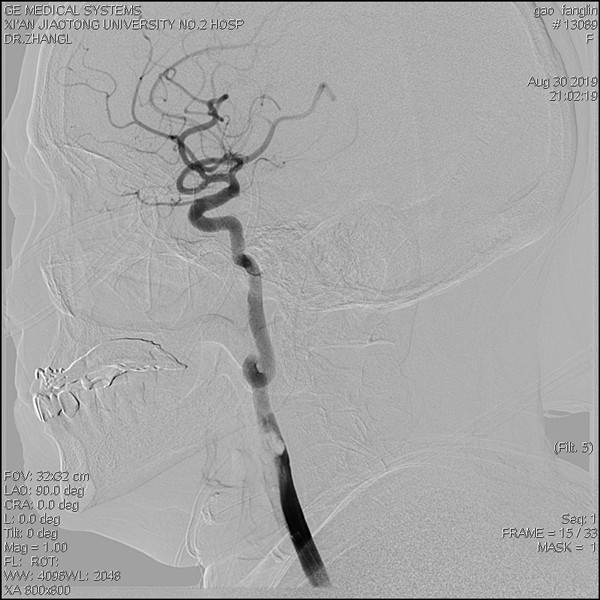

取栓术后颈内动脉内血栓消失

造影见右侧颈内动脉起始段内大量血栓